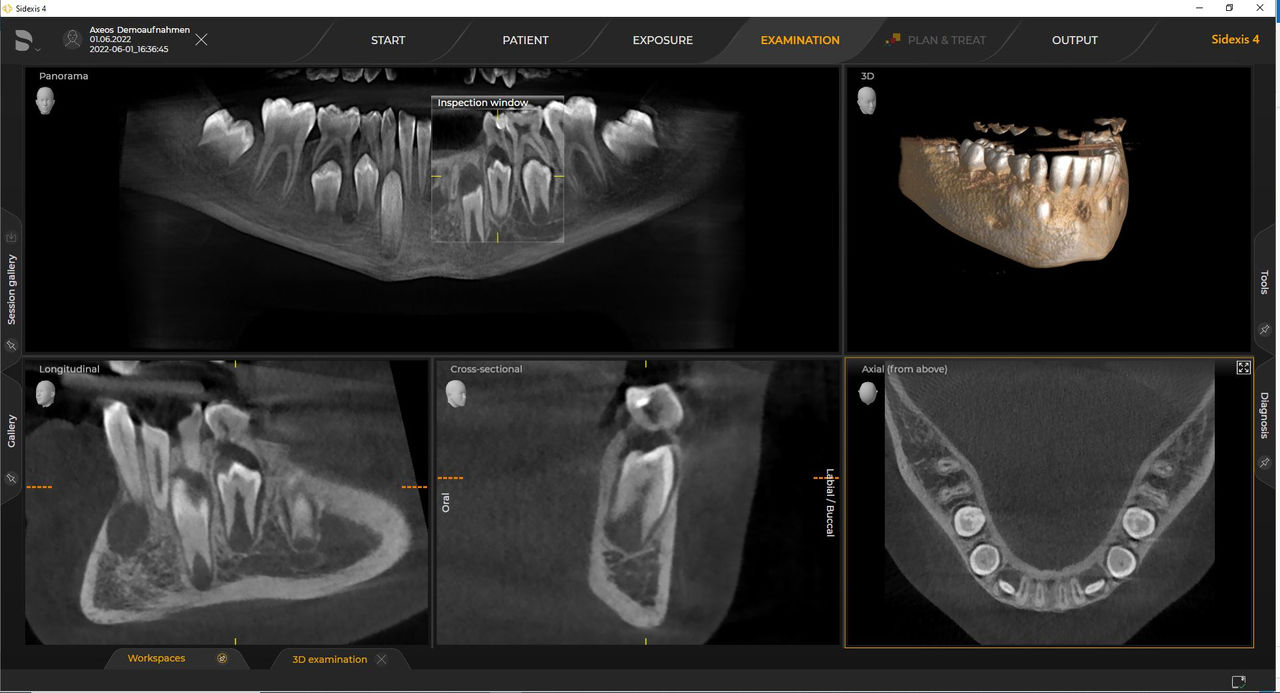

Los requisitos siguen aquellos del software de procesamiento de imágenes de Sidexis 4 y Axeos. Para obtener más detalles, consulte los requisitos del sistema Sidexis 4 y los requisitos de instalación de Axeos.

Las unidades 3D de Dentsply Sirona funcionan exclusivamente con Sidexis 4. Sin embargo, la migración de datos de Sidexis XG a Sidexis 4 es muy fácil. Sidexis 4 permite una experiencia digital completa con las últimas herramientas.